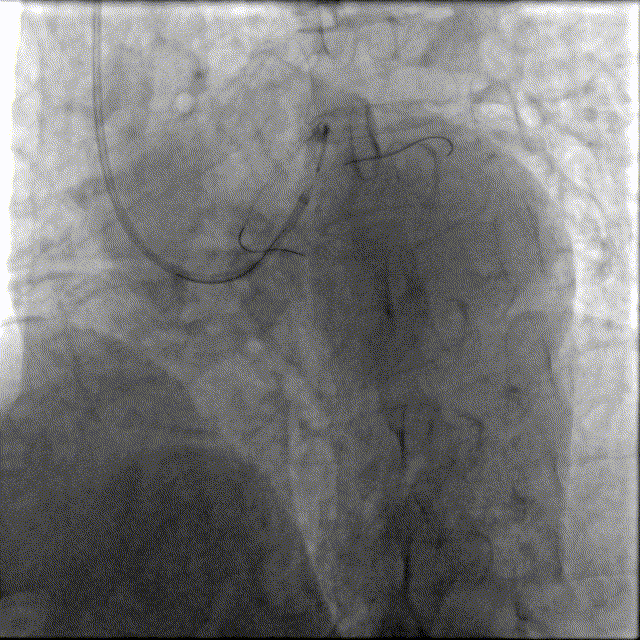

冲击波导管送至左前降支,由中段至开口依次以4atm压力初始冲击扩张,6atm压力巩固扩张,共冲击扩张10秒×8个周期,可见球囊逐渐膨胀充分。此阶段在处理前降支开口时预置回旋支保护导丝。

预处理效果满意。